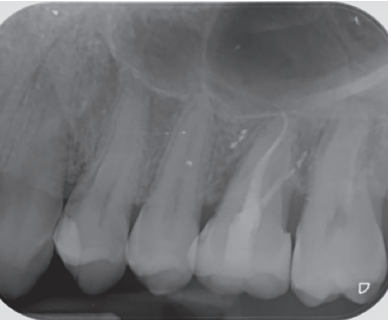

There were no medical-surgical antecedents of interest in his medical history, without known drug allergies or unhealthy habits. No relevant data was found on the extra oral examination. In the intraoral examination, non-restorable teeth were seen in the 2.6 and 4.6 position and the presence of retained lower third molars. (Figures 1 and 2).

In the radiograph examination, through a panoramic radiograph, both lower third molars were seen retained in horizontal position (Figure 3), and apical radiolucent images in positions of 2.6 and 4.6. The cone beam scan evaluated the root morphology of the left upper third molar and the size of the apical radiolucent lesion of the left upper first molar (Figure 4), necessary data to assess the degree of adaptation of the donor tooth in the recipient bed.

associated with the root remains of 2.6 and the conical root of 2.8 are seen.